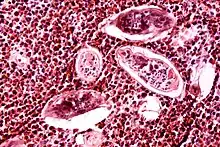

Diagnosis

_histopathology.JPG.webp)

Identification of eggs in stools

Diagnosis of infection is confirmed by the identification of eggs in stools. Eggs of S. mansoni are about 140 by 60 µm in size and have a lateral spine. The diagnosis is improved through the use of the Kato-Katz technique, a semiquantitative stool examination technique. Other methods that can be used are enzyme-linked immunosorbent assay, circumoval precipitation test, and alkaline phosphatase immunoassay.[47]

Microscopic identification of eggs in stool or urine is the most practical method for diagnosis. Stool examination should be performed when infection with S. mansoni or S. japonicum is suspected, and urine examination should be performed if S. haematobium is suspected. Eggs can be present in the stool in infections with all Schistosoma species. The examination can be performed on a simple smear (1 to 2 mg of fecal material). Because eggs may be passed intermittently or in small numbers, their detection is enhanced by repeated examinations or concentration procedures, or both. In addition, for field surveys and investigational purposes, the egg output can be quantified by using the Kato-Katz technique (20 to 50 mg of fecal material) or the Ritchie technique. Eggs can be found in the urine in infections with S. haematobium (recommended time for collection: between noon and 3 PM) and with S. japonicum. Quantification is possible by using filtration through a nucleopore filter membrane of a standard volume of urine followed by egg counts on the membrane. Tissue biopsy (rectal biopsy for all species and biopsy of the bladder for S. haematobium) may demonstrate eggs when stool or urine examinations are negative.[48]

Tissue biopsy

If other diagnostic methods of schistosomiasis have failed to detect the infection, but there is still a high suspicion for schistosomiasis, tissue biopsy from the rectum, bladder, and liver can be obtained to look for schistosome eggs within the tissue samples.[19][26]